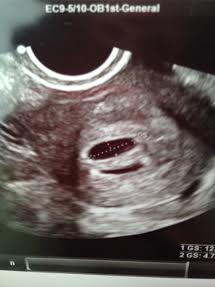

TWINS!!! 2 beautiful sacs looking just how they are supposed to! We go back next Friday to hear the heatbeats. HOLY CRAP!! It's not official until I hear the heartsbeats I know, but I had to tell someone!

A&B are below! 5w3d!

Beta #1 12dpo - 164 & progesterone - 89!, Beta #2 16 dpo - 1189, 5w3d - u/s shows TWINS!